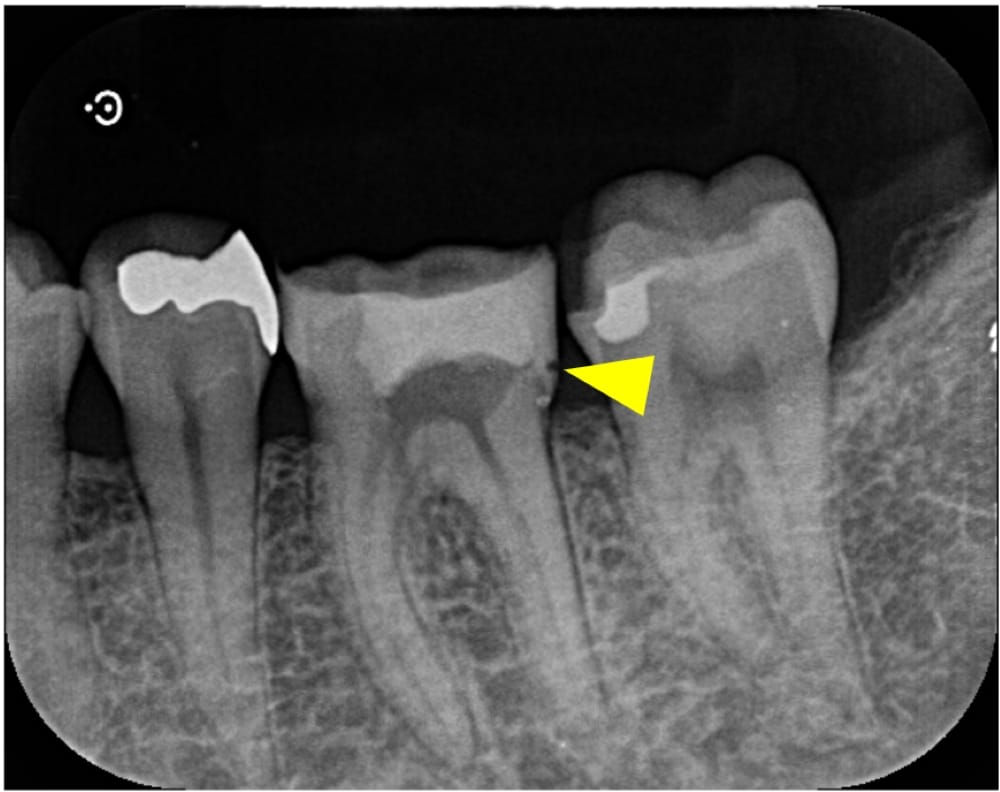

レントゲン・CT画像にて、右下第一大臼歯の根尖部に、明瞭な骨吸収像が認められます。来院時には根管治療の途中の状態でしたが、内部に虫歯が残っており、感染源が取り除けていない状態でした。急性炎症に対して確実な即効性がある治療はありませんが、最大限感染を除去し、細菌の侵入を防ぐことを第一に応急対応を行いました。

術後6ヶ月が経過時点でのレントゲン・CT画像では、もともとはっきりと写っていた根の先の黒い部分は消失し、骨の回復が認められます。痛みも全くなくなり、治癒していると判断し、最終補綴(かぶせもの)を行うことになりました。